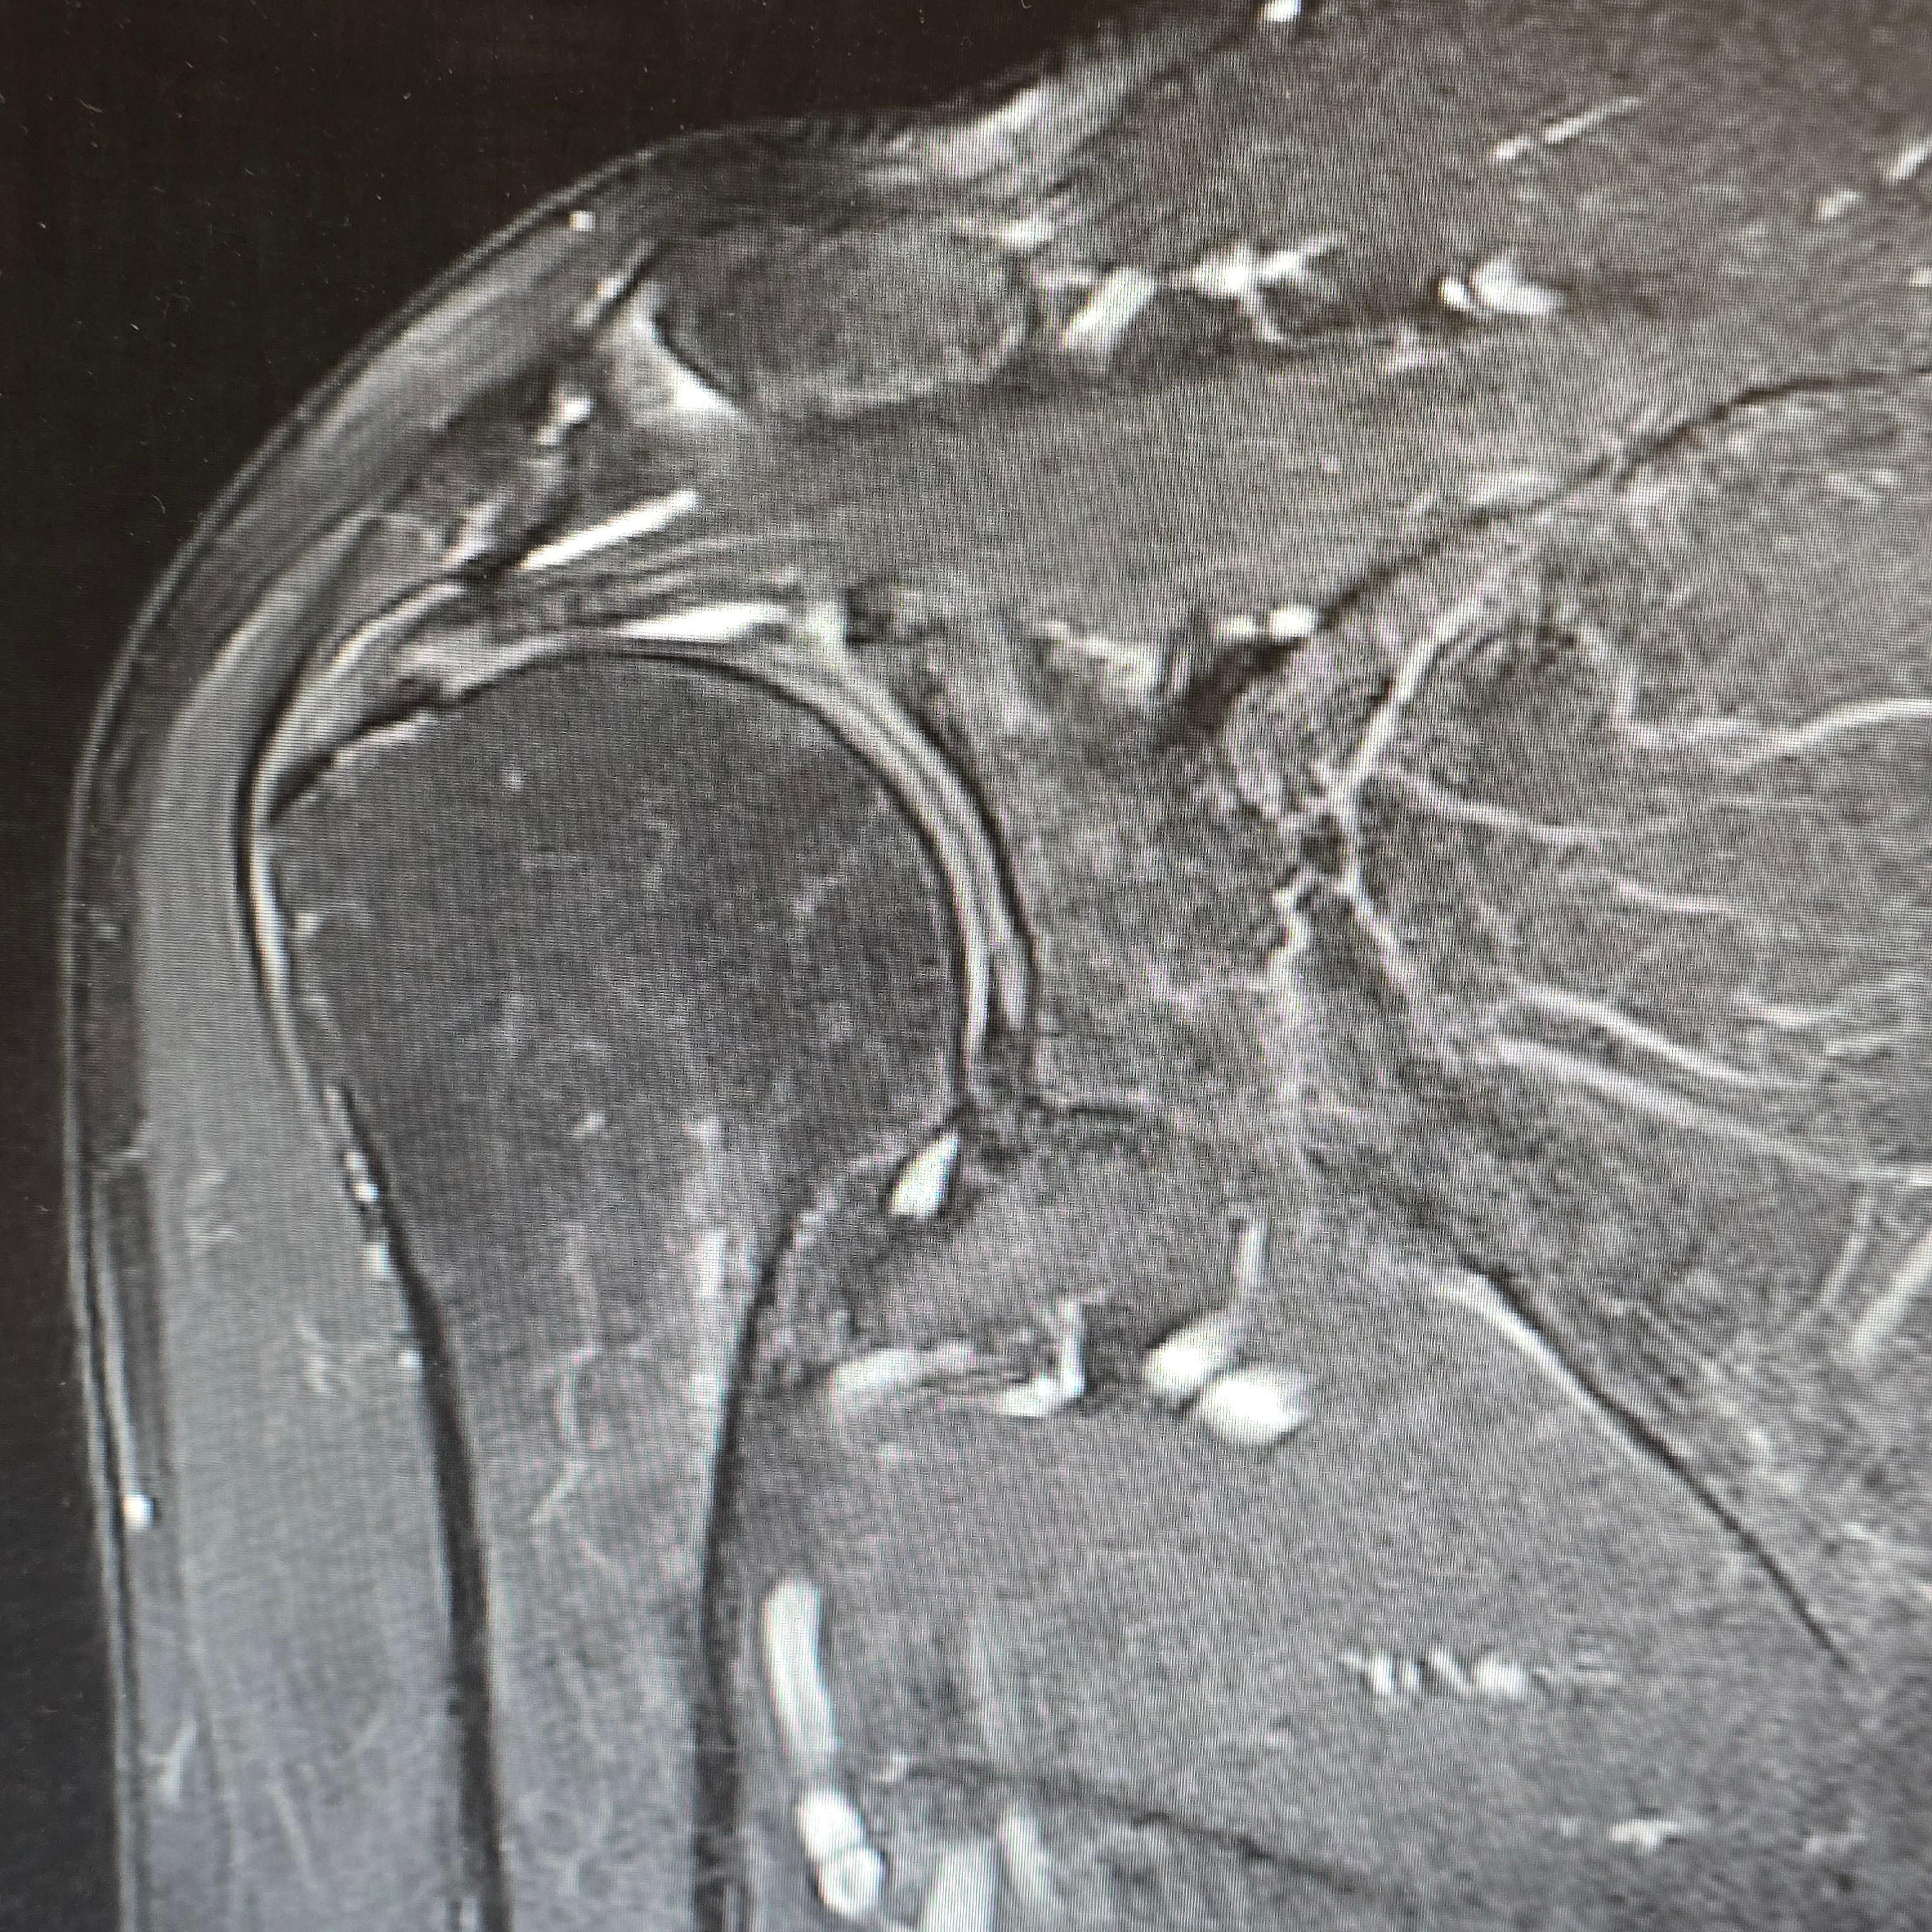

X-ray, MRI, 초음파 검사: 회전근개 손상 여부나 염증 유무를 확인